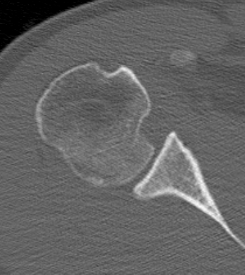

CT scan

Confirms dislocation

Reverse Hill Sachs

Humeral head defect

- caused by impaction of anterior humeral head on posterior glenoid

- intra-articular

- measured as a percentage of the articular surface

Lesser tuberosity fractures

Posterior glenoid fractures / bony bankart